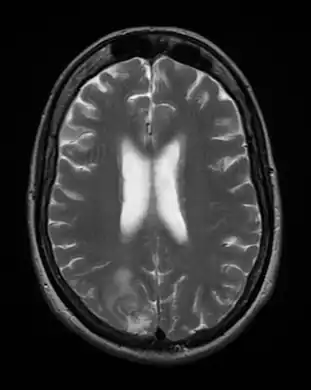

Cerebral toxoplasmosis (with primary involvement in the right occipital lobe) -

Cerebral toxoplasmosis -

Cerebral toxoplasmosis